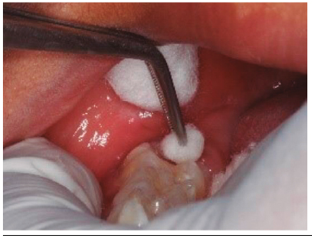

Luego de considerar las medidas de bioseguridad se procedió con el tratamiento de la pieza 46 (Figura 1), se realiza aislamiento relativo por la falta de erupción total de la pieza y la excesiva sensibilidad del paciente, aplicó brix 3000 (gel enzimático para la remoción a traumática de tejido infectado) (brix SRL Argentina), sobre las superficies infectadas de la pieza 46, luego de 2 minutos, con una cureta de dentina (Mayleffer N° 46) eliminamos estructura dental con HIM (Figura 2), se lavó con agua, y secó, se realizó desproteinización de la cavidad dentaria con una bolita de algodón embebida con hipoclorito de sodio al 5% por 30 segundos, y se enjuagó con una bolita de algodón embebida en agua, secado con bolitas de algodón (Figura 3), luego de cambiar el aislamiento relativo; se aplicó el adhesivo de 7ma generación Palfique Bond (Tokuyama), por la sensibilidad del paciente, se airea, fotocura por 20 segundos (Figura 4), y se aplica Giómero fluido F00 de reconstrucción (Beautifil Flow Plus de Shofu inc.), dando forma con el bruñidor para resina cabeza de huevo y se fotocuró por 20 segundos (Figura 5). Se utilizó el Giómero fluido F03 de sellado de fosas y fisuras (Beautifil Flow Plus de Shofu inc.) fotocurando por 20 segundos (Figura 6). Finalmente se comprueba el ajuste oclusal con una fresa cilíndrica plana (108-009) eliminando excesos y porosidades (Figura 7a).